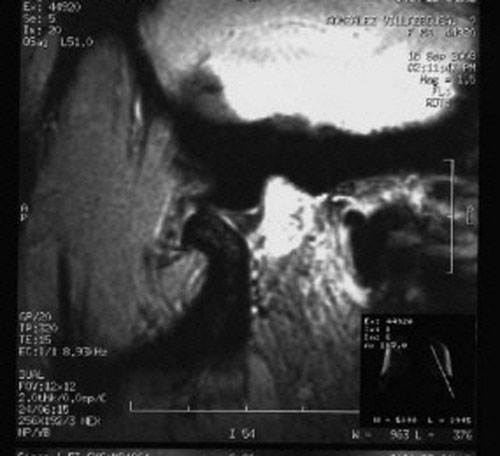

RMN de ATMs (17-09-2008): Dentro de la normalidad.

– ATMs dentro de la normalidad.

PRUEBAS DIAGNOSTICAS COMPLEMENTARIAS: